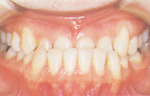

悪い歯並びを総称して不正咬合といい、心身に大きな影響を与えます。 正常咬合になれば多くの問題が解決します。上下の歯が正しくかみ合い、歯の接触面積が広くなり、食べ物の消化、吸収が促進され、心身ともに健康な成長発育を示します。

乱ぐい歯・八重歯(叢生)

あごが小さかったり、あごに対して歯の幅が大きい場合に起こります。 歯の生える場所が足りないので、凹凸に生えたり、重なり合って生えています。